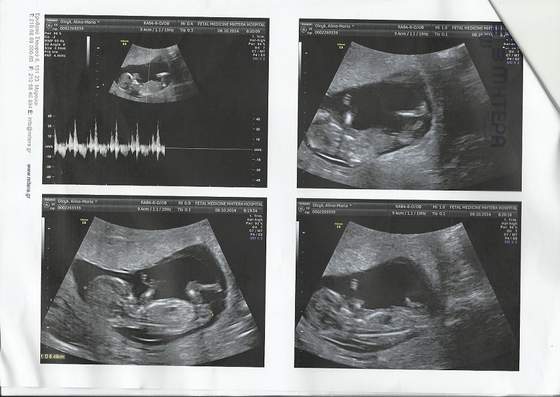

a to moje cudenko z wczoraj :)

12t3d, 63.3mm, puls 159

ale za malo byl ruchliwy (do oznaczenia kilku parametrow nie chcial pozowac), wiec za tydz powtorka :)